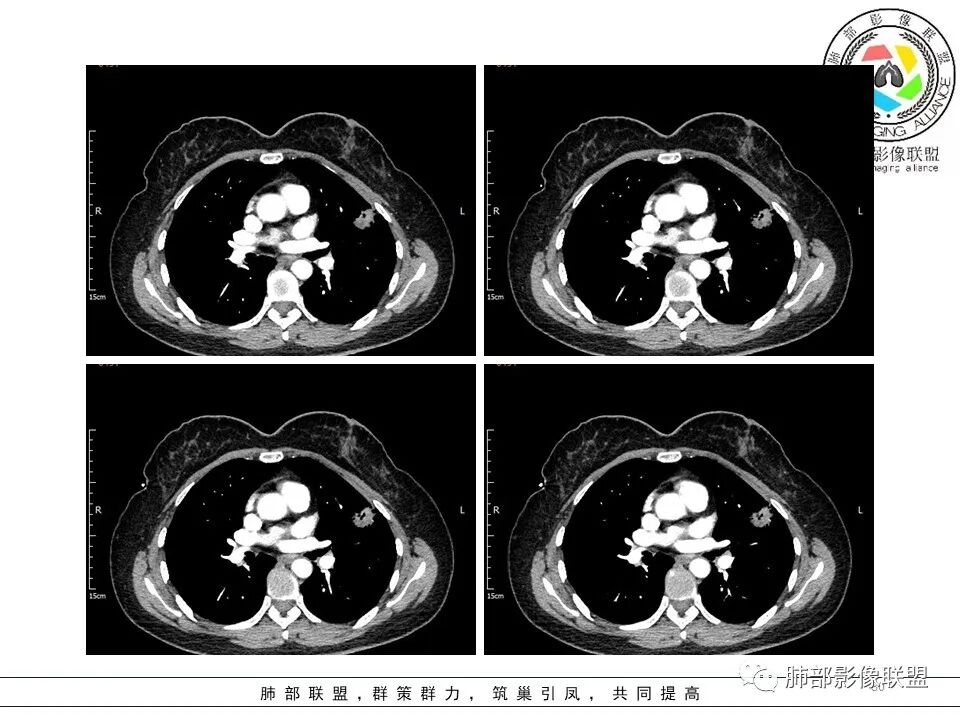

左肺上叶ggo,短毛刺,空泡征,6个月后复查病灶似变大,有轻度不均质强化,腺癌?胸膜下粟粒结节,无变化,良性?

分叶结节,内部结构杂乱,边缘板刷样毛刺,GGO边界清楚

胸膜牵拉

月牙铲?

常规要考虑腺癌

左肺上叶胸膜下不规则结节影,分叶、粗短毛刺,胸膜牵拉等,像个“刺头”。

未见钙化,也未显示液化坏死或空洞。

与支气管相关,但取层未能显示支气管进入情况。

1.病灶周围向几个方向膨出的边界清楚的磨玻璃影,这些磨玻璃影时隔几个月依然,几乎可以排除出血及一般的炎性改变。

2.病灶的胸膜牵拉线与其间病灶胸膜侧的磨玻璃边构成朝向胸壁的“月牙铲”结构,这种影像学表现某种程度上反映出病理学特征——病灶收缩+小叶间隔阻挡。

3.病灶实性密度区强化明显,这有助于我们区分一些其他类似病灶,如结核灶等!

4.邻近未见树芽征及卫星灶等。

结合临床,应当高度怀疑浸润性肺腺癌!